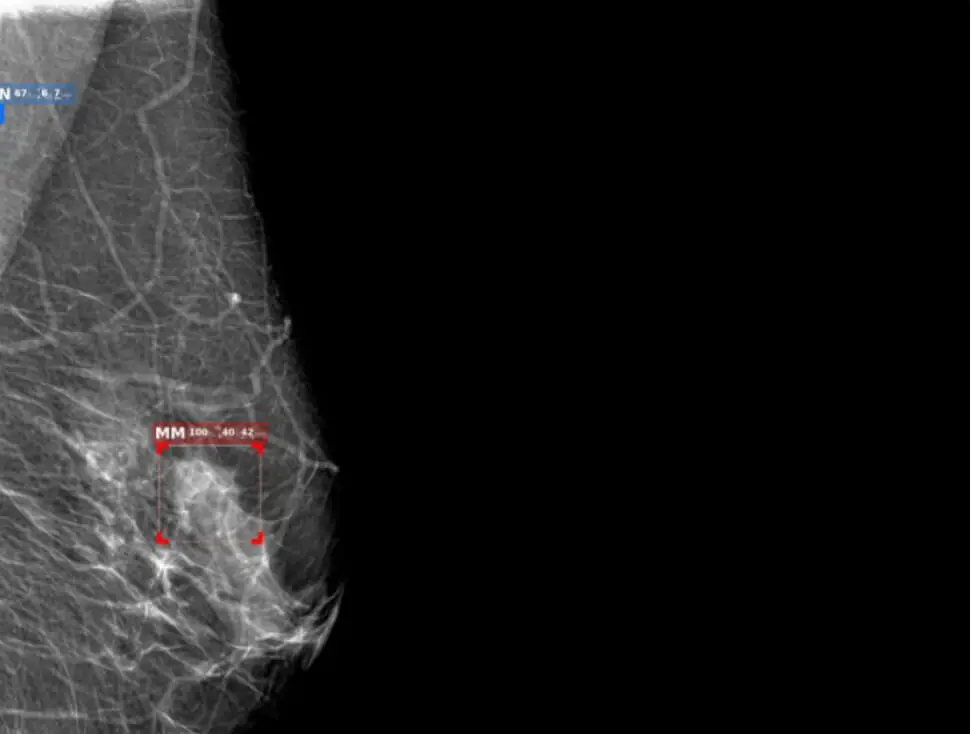

L CC R CC

L MLOR MLO

An AI-powered solution efficiently detects pathologies in medical imaging, including cancer, cancer nodules in the early stages. It supports X-rays, CT scans, and MRIs, reducing diagnosis time and enhancing hospital capacity by streamlining workflows.